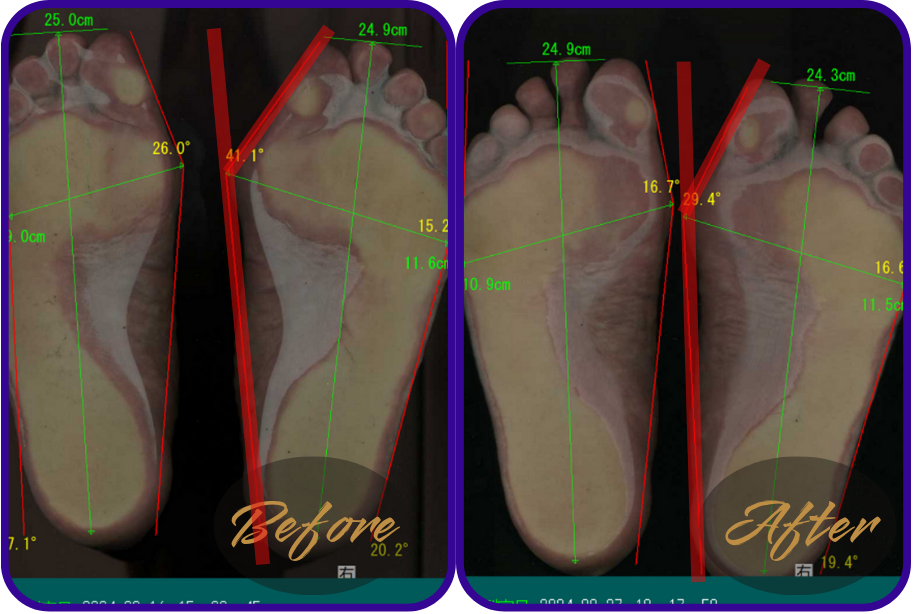

姿勢や歩き方の改善判断は、足裏の圧力画面や外反母趾の数値で出します。

ダイエットと同じで、体重やサイズを数値でみないとダイエットに成功したかわからないですものね。

↑39,5°あった外反母趾が27,7°まで改善。

↑足幅10,9㎝あったのが9,7㎝まで細くなった。

歩行整体に通われた患者様の足裏の様子をご紹介します。

※テーピングやゴムバンドなどは使用しておりません。整体と姿勢歩き方レッスンのみです。

↑60代女性

お悩み…足の疲れ、足のつり、腰痛

感想…「いつの間にか足はつらなくたったし、腰痛は減った。腰痛があるときは、姿勢のポイントをまもっていないことに気が付けるようになった。」